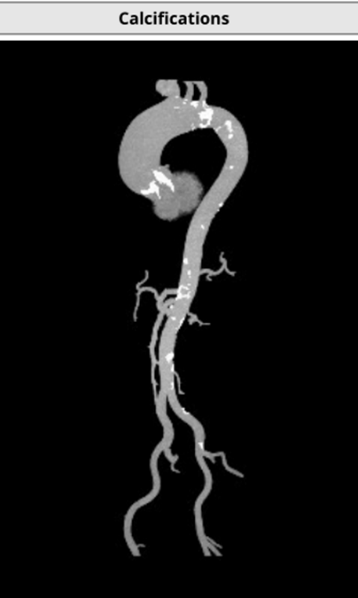

主动脉瓣为type -I 型二叶瓣,右无瓣叶嵴部融合伴有钙化并向窦部延伸16.0mm,瓣环平面可见钙化斑块向左室流出道延伸约12.3mm,瓣叶极重度钙化,中重度增厚;左冠窦较右无冠窦略偏大,右无冠窦基本等大;右冠脉开口高度可,左冠脉开口处可见瓣叶钙化斑块;心室大小可,室壁厚度可,中重度横位心;大血管走行自然,内径可,升主动脉扩张,主动脉弓部角度可,弓部、降主、腹主、左髂总动脉可见少-中量钙化斑块。